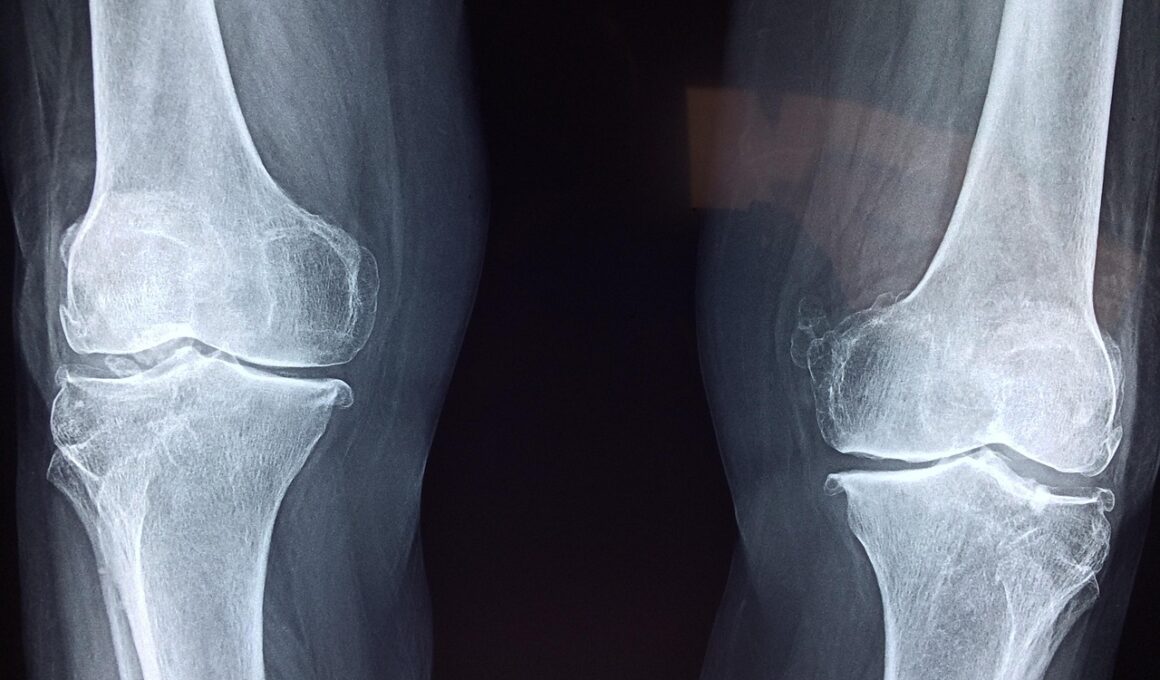

Speed skaters face distinct types of injuries due to their unique movements and techniques. One of the most common issues is knee injuries, which arise from the repetitive strain placed on this joint. Ligament injuries, particularly to the anterior cruciate ligament (ACL), can be detrimental, significantly hindering an athlete’s career. Another prevalent injury involves ankle sprains, occurring from sudden changes in direction or loss of balance. Additionally, overuse injuries like tendinitis can develop in the patellar tendon, causing pain and weakness. Skaters often experience shoulder injuries due to falls, making proper protective gear crucial in mitigating these risks. Advanced techniques in physical therapy are increasingly focusing on recovery protocols tailored specifically for speed skating-related injuries. Utilizing ice therapy, ultrasound treatments, and rehabilitation exercises designed for skaters can greatly enhance recovery times. Furthermore, gym workouts emphasize strengthening core and lower body muscles used during races, reducing overall injury likelihood. Awareness and education about maintaining body mechanics remain essential for aspiring athletes and can play a pivotal role in injury prevention.

One cutting-edge innovation in injury assessment is MRI scanning technology. This non-invasive approach allows medical professionals to visualize internal injuries without surgical intervention. Utilizing 3D imaging greatly enhances the accuracy of diagnoses, providing insight into the extent of soft tissue injuries and bone fractures. Additionally, ultrasound technology is gaining traction as it can quickly assess joint injuries, offering immediate feedback to sports physicians. Medical personnel can use ultrasound for guided injection therapy, providing targeted relief for conditions like tendinitis. Moreover, advanced laboratory testing can identify specific biomarkers that indicate injury risk in an athlete, paving the way for tailored training regimens. This blend of technology not only aids in detecting ongoing problems but also provides data necessary for long-term athlete monitoring. Coaches and trainers can adjust training intensities based on an athlete’s biomechanical data, enhancing performance while warding off injuries. Emphasizing preventive care through technology continues to reshape the sporting landscape while keeping athletes safe. As technology progresses, its application will only continue to grow, delivering better insights into injury prevention and treatment for speed skaters.